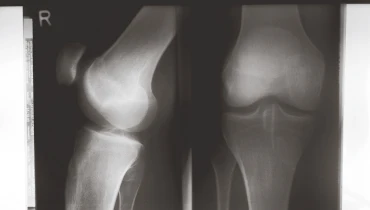

Подготовка к остеосинтезу надколенника

В рамках подготовки нужно понять точный вид перелома, оценить кожу, связки и сухожилия, спланировать доступ и конструкцию. На консультации врач объясняет, как будет проводиться операция, какие риски и как они минимизируются, когда начнется ЛФК и чего ждать по срокам. Диагностический этап включает рентген в двух проекциях. При спорной геометрии добавляется КТ для уточнения суставной поверхности. В день вмешательства обсуждаем обезболивание, профилактику тромбозов и антибиотикопрофилактику, чтобы все этапы прошли без задержек.

Рентген/КТ для контроля высоты, смещения и угла; осмотр кожи и сухожилия квадрицепса. Планируем методику: проволока, спица, винт или пластина; согласовываем сроки начала сгибаний.